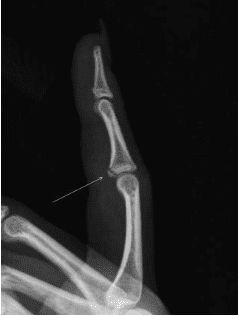

[Cleveland Cavaliers official] Cavaliers guard Keon Ellis injured his left index finger in Wednesday night’s game at Milwaukee. A postgame examination by the Cavaliers’ medical staff, followed by X-rays taken at the arena, confirmed a non-displaced volar plate avulsion of his left index PIP joint.

Ellis will undergo treatment and continued evaluation and listed as QUESTIONABLE tonight at Detroit. His status will be provided as appropriate.